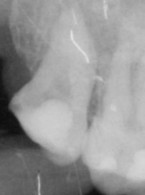

Leczenie endodontyczne drugiego zęba trzonowego szczęki z pojedynczym korzeniem i pojedynczym kanałem korzeniowym

Zobacz więcej